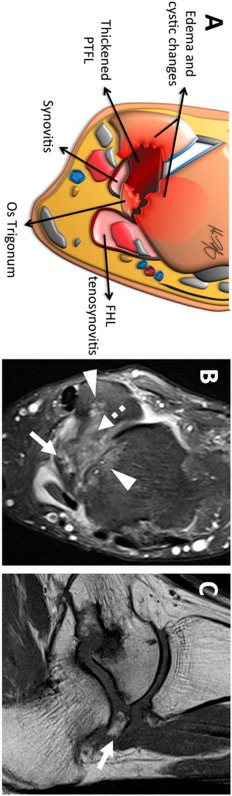

图12。

后踝关节撞击的侧位矢状位图示:(a)足底弯曲的踝关节伴有相关的os三角,后软组织被卡压,包括距骨后韧带(PTFL)和相关的滑膜炎。(b) 由于两者关系密切,刺激和增厚的屈肌支持带可引起长屈肌肌腱刺激和腱鞘炎。

MRI具有优越的软组织对比度,在评价后踝关节疼痛方面起着非常重要的作用。一个主要特征是距骨、跟骨或os三角区的骨髓水肿(低T1和高T2信号)(图13)。其他特征包括软骨结合处信号增强、相关滑膜炎和后韧带增厚(图14),以及后距下神经节或胫距神经节存在的可能性。

图13。

一位47岁男性,患有慢性踝关节疼痛,在足底屈曲过程中恶化,与后部撞击一致:(A)轴位图,(b) 轴位液敏图像和(c)矢状位T1加权像显示os三角(箭头)退化,距骨后韧带(PTFL)增厚(虚线箭头),距骨和腓骨水肿/囊性改变(箭头)。